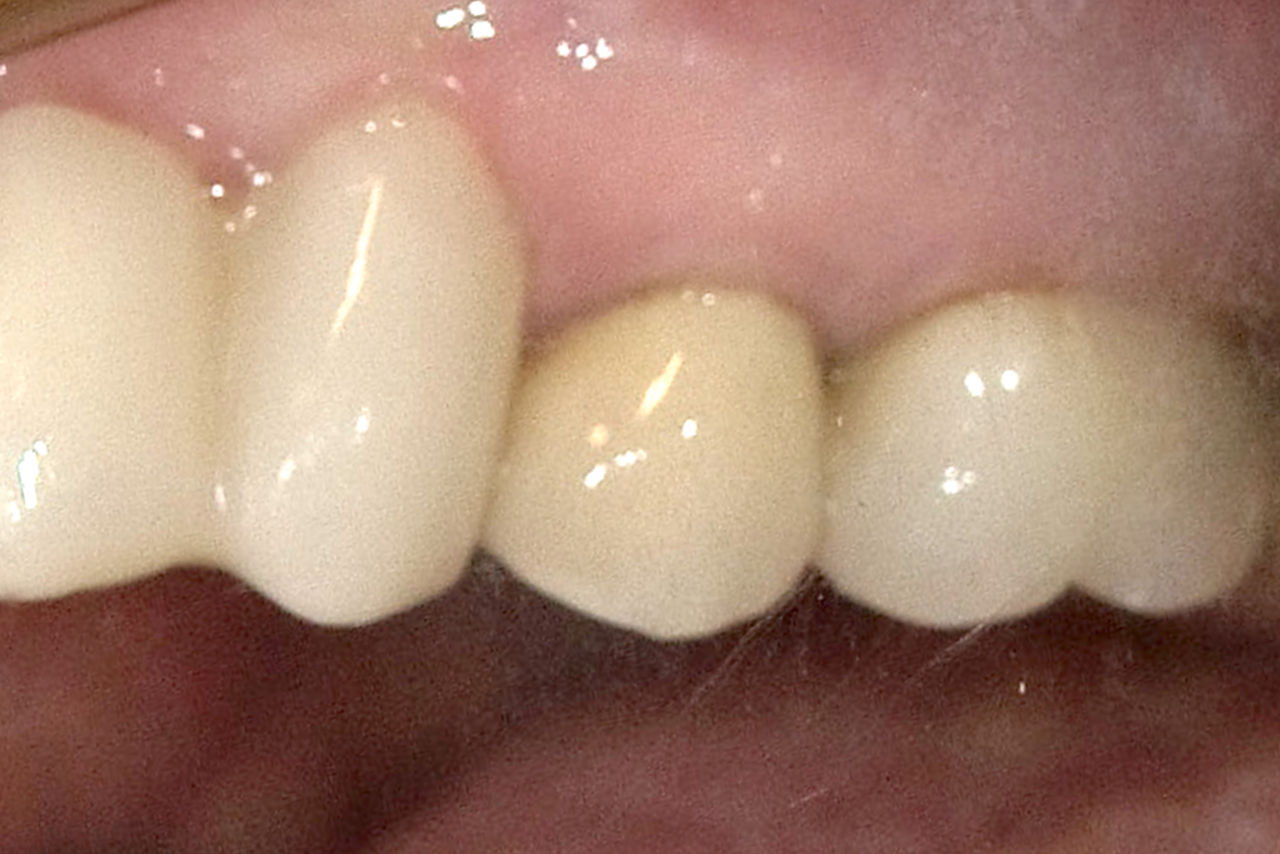

After

Highly esthetic single-tooth restorations with implants and chairside fabricated anterior crowns.